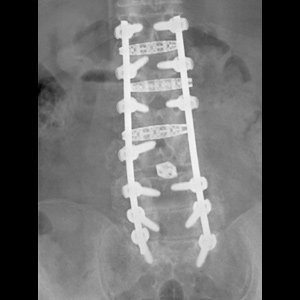

Spinal stenosis (Lumbar) Spinal stenosis (Cervical) Spinal stenosis (Thoracic) Lumbar Disc Herniation Spondylolisthesis Cervical Foraminal Stenosis Vertebroplasty Lumbar Fusion Anterior Cervical Fusion (ACDF) Posterior Cervical Fusion Thoracic Fusion Revision Lumbar Fusion Surgery Facet Joint Cyst Spinal Tumour Minimally Invasive Lumbar Fusion (XLIF) Minimally Invasive Lumbar Fusion (ALIF) Lumbar Fusion (TLIF) Thoraco-lumbar Fusion Lumbar Corpectomy Complex Lumbar Spine Surgery (Spino-pelvic fixation) Complex Cervical Spine Surgery Complex Thoracic Spine Surgery Occipito-cervical Fusion Minimally invasive surgery for thoracic disc herniation Other Related Topics